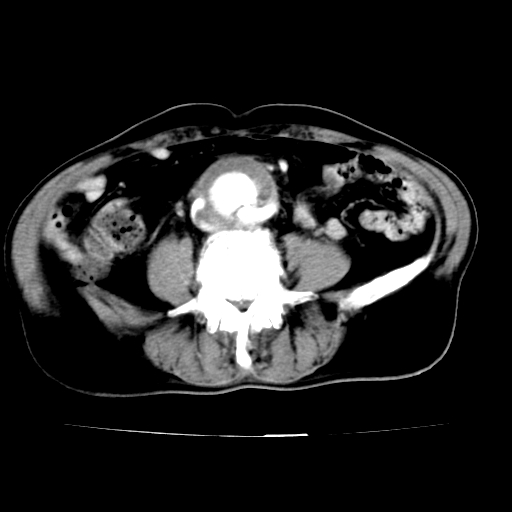

标题: V0243:右髂总动脉瘤附壁血栓形成?破裂?动静脉瘘? [打印本页]

标题: V0243:右髂总动脉瘤附壁血栓形成?破裂?动静脉瘘?

男,75岁,腹痛月余,彩超发现脐周腹主动脉异常回声。临床诊断:腹主动脉瘤。

ct诊断:右骼总动脉囊性动脉瘤并瘤内附壁血栓形成,与下腔静脉之间形成动静脉瘘。

请问各位老师:能排除动脉瘤破裂的可能吗?

各位老师注意到下腔静脉的充盈缺损了吗?注意到动静脉漏了吗?

此病例平扫图像已发,请大家看看!

当时是扫描的标准动脉期,可是下腔静脉与腹主动脉同步强化且幅度一致。所以我想动静脉瘘是存在的。